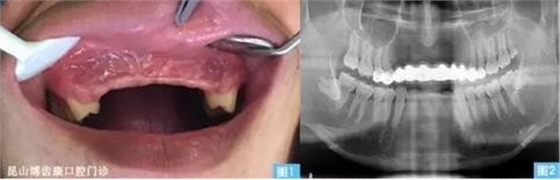

男,31歲

外傷后上前牙缺失約十年,要求種植修復(fù)。

(1)13、12、11、21、22、23缺失

(2)25殘根

(3)下頜左右第三磨牙近中水平阻生

圖1圖2:患者主訴外傷后上前牙缺失約十年,要求種植修復(fù)。全景片發(fā)現(xiàn)缺牙區(qū)牙槽骨吸收嚴(yán)重,上唇部塌陷。